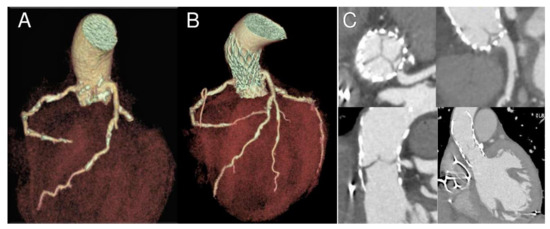

The index procedure was uncomplicated with no procedural atrioventricular block or embolic events and negligible aortic regurgitation. CT scan at the moment of readmission showed a marked change in the size of the annulus (preoperative calculated annular area 367 mm2, post-TAVR 272 mm2, change from baseline −95 mm2) and in the height of the coronaries relative to annulus (3 mm for the right coronary and 5 mm for the left coronary; change from baseline −7 mm and −6 mm respectively) (Table 1). Coronary ostia obstruction caused by pre-existing root calcifications was demonstrated and confirmed by angiogram, which showed an ostial stenosis of both the left main stem and the right coronary ostia with paravalvular leakage of the bioprosthesis (Figure 2, Figure 3 and Figure 4).

Figure 2. Nine-month follow-up gated CT scan demonstrating bioprosthesis malposition in respect to left main coronary. 3D reconstructions in longitudinal and cross-section before (A) and after the procedure (B,C). Please note coronary ostia proximity with calcifications and ostial stenosis due to partial obstruction by a portion of the THV frame (C).

Figure 3. Nine-month follow-up gated CT scan demonstrating bioprosthesis malposition in respect to right coronary. 3D reconstructions in longitudinal and cross-section before (A) and after the procedure (B,C). Please note ostia proximity with calcifications and ostial stenosis due to partial obstruction by a portion of the bioprosthesis frame (C).